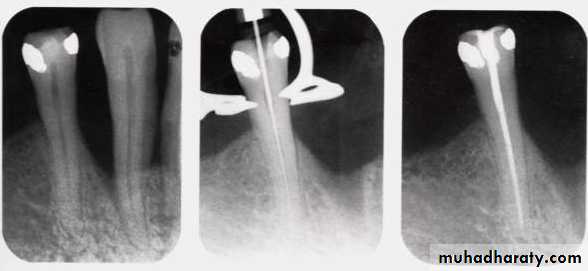

Endodontic procedures

Design options

Supporting elements (non-retentive)• Roots sealed with amalgam, composite, or glass ionomer cement.

• Gold root copings without attachments.